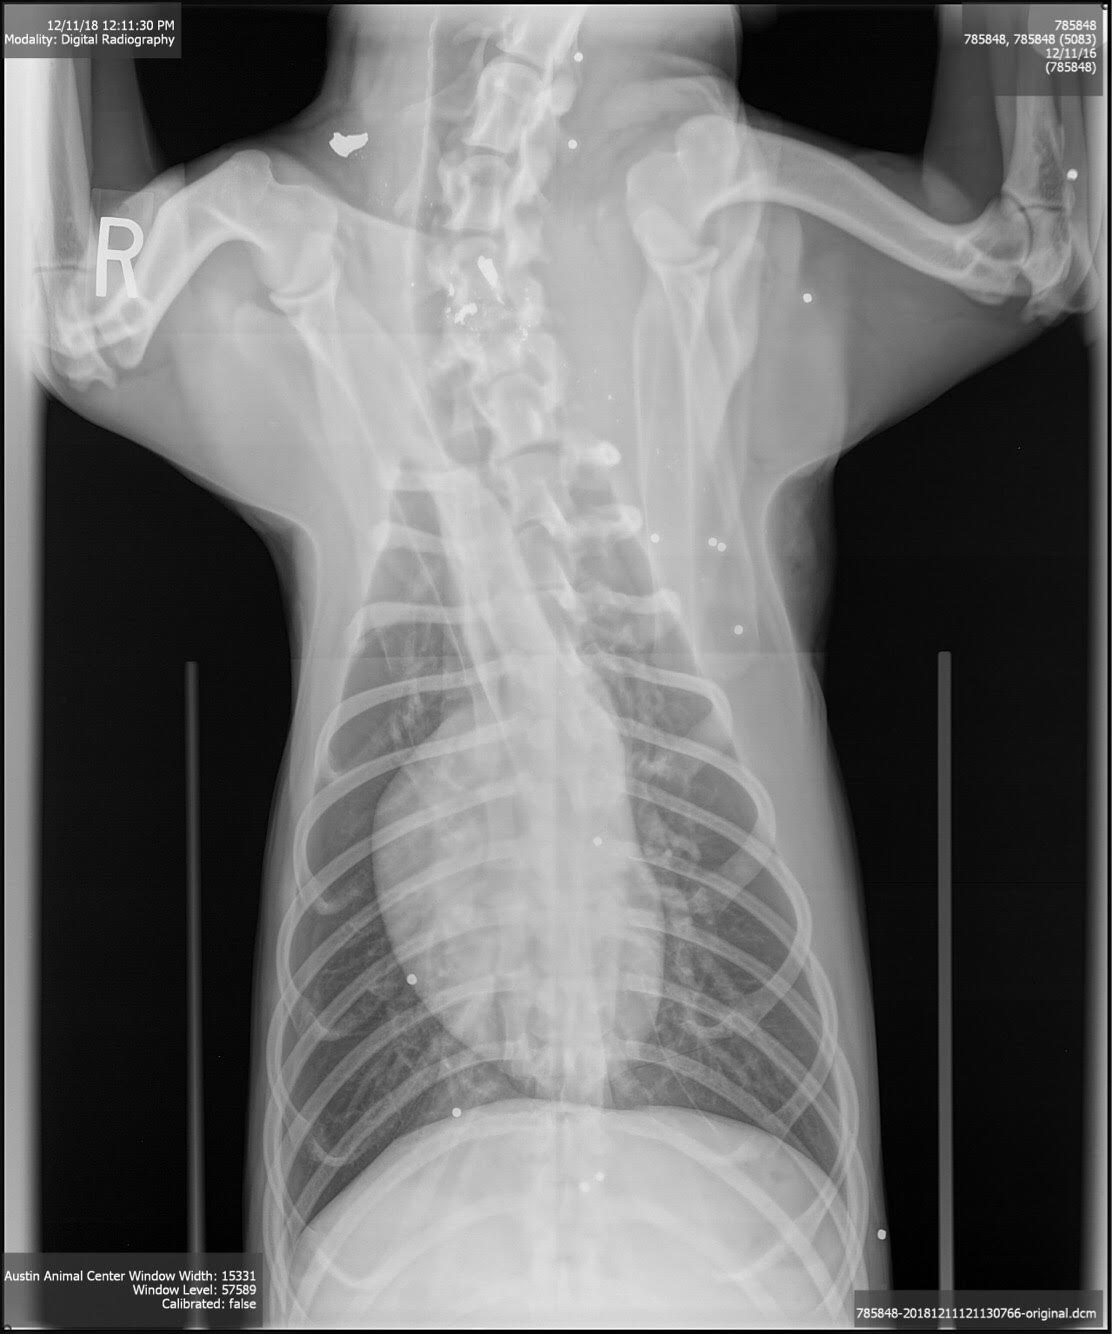

While we don’t know exactly how or why he was shot, we do know that the bullet hit Jolly in his front right leg and then shattered throughout his body. With most of his severe pain centralized to the area around the initial point of entry, our clinic is working to manage his pain as well as to prevent infection with the help of his medical foster while determining the best care plan for Jolly. His x-rays have been sent to an orthopedic specialist to determine if his leg will need to be amputated, or if surgery to remove the bullet fragments will be the best course of action to relieve Jolly of his pain and help him begin the long road to recovery – both physically and emotionally.